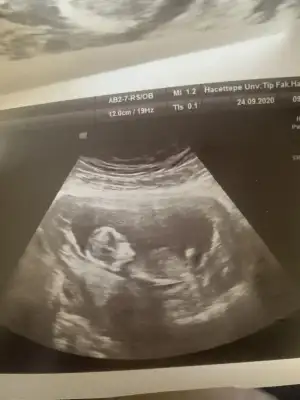

Nubu yüksek görünüyor sanki net değil karışık görünüyor emin olamadimBaşka usg yok doktor kıza benziyor demisti ama net değil demisti

Kız gibi sanki kaç haftalık usgler 11 12 13 haftalar olmalı

12 haftalıkKız gibi sanki kaç haftalık usgler 11 12 13 haftalar olmalı

Emin olamadım başka USG varsa paylaşın sanki erkek gibi gibi ama emin değilimMerhaba 11+0 tahminde bulunur musunuz?

Birde bu var :)Emin olamadım başka USG varsa paylaşın sanki erkek gibi gibi ama emin değilim

Net değil olursa 12 13 haftalar paylasirsinBirde bu var :)

Merhaba tahmininiz doğru çıktı doktorumuz %95 kız dediDr tam -----+ nubtan geçmiş ölçümü emin değilim sanki kız 11 12 13 haftalar olursa paylasin